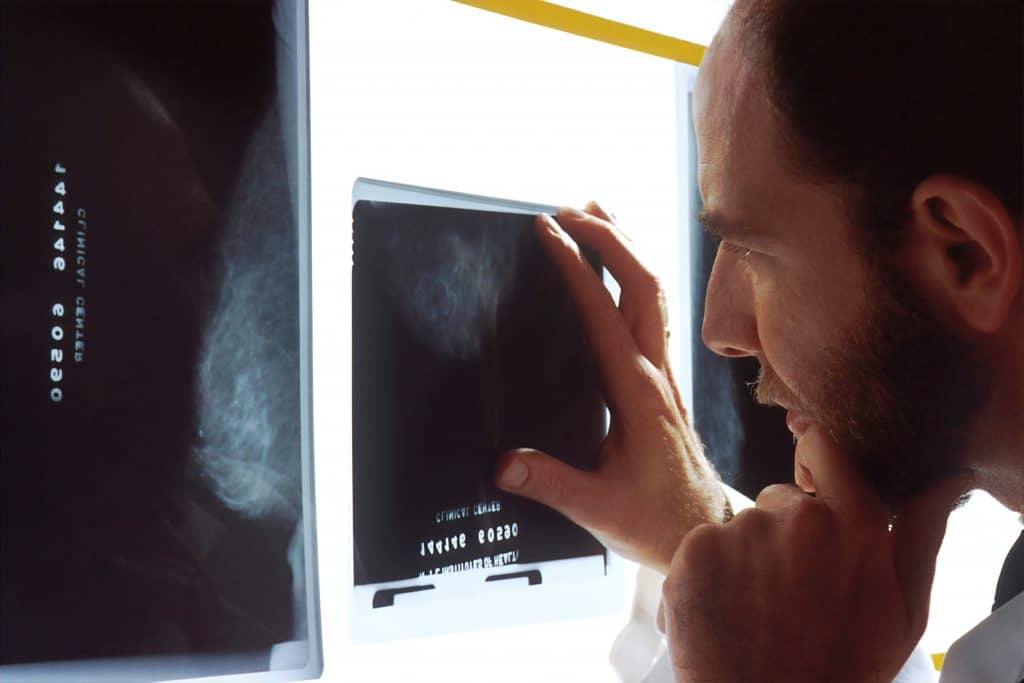

A mammogram is a type of X-ray. It works by sending a low dose of radiation through your breast. Different types of body tissue block different amounts of radiation. The mammogram equipment collects any radiation that passes the whole way through your breast. The resulting image is a grayscale picture of the inside of your breast.

Radiation passes through normal breast tissue easily, creating dark shapes on your mammogram image. Breast cancer tissue, on the other hand, blocks the radiation, resulting in white forms on the image. If you have abnormal white patches on your mammogram, it could be caused by a tumor.

Who interprets mammograms?

A radiologist reads mammograms. Radiologists are medical doctors who have completed additional specialty training in diagnosing and treating diseases with medical imaging studies, including mammograms, X-rays, MRIs, CT scans, nuclear medicine, and PET scans.